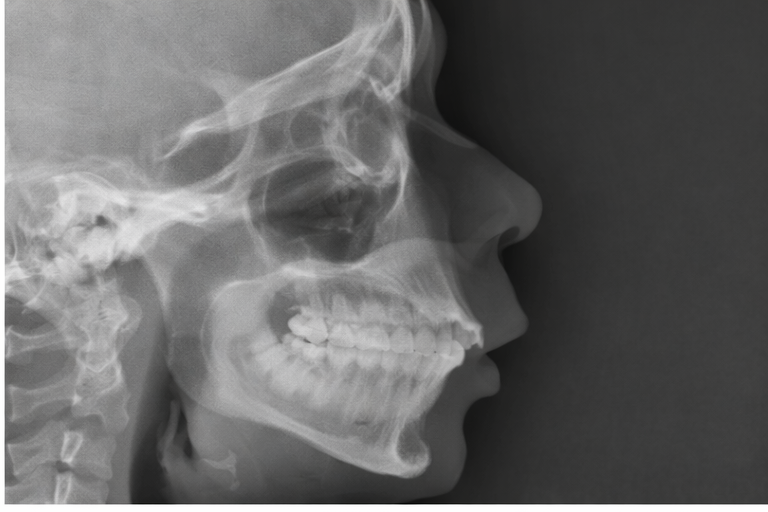

Diagnóstico en la Clínica Dental Ramis Gandía (Inca, Mallorca)

Estudio completo de ortodoncia y perfil

Ante la sospecha de retrognatia mandibular, realizamos:

-

Exploración clínica detallada.

Fotografías intraorales y extraorales.

Radiografías y estudios cefalométricos.

Registros digitales con escáner intraoral.

Con todo ello, valoramos la relación entre maxilar superior, mandíbula y base del cráneo, así como la posición de los dientes, encías y articulación temporomandibular (ATM).